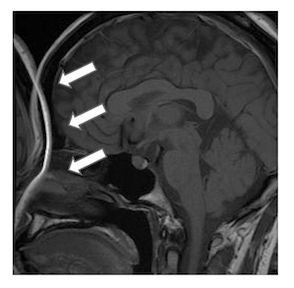

14-48 MR画像を以下に示す.描出されているものはどれか。3つ選べ。

MRI認定 総集 ランダム